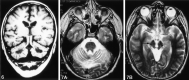

Results: We noted osseous lesions in the craniofacial or skull bones in 56% of patients, meningeal lesions in 29%, and choroid-plexus involvement in 6%. In the hypothalamic-pituitary region, infundibular thickening occurred in 50%; pronounced hypothalamic mass lesions in 10%; and infundibular atrophy in 29%. The pineal gland had a cystic appearance in 28%, and pineal-gland enlargement (>10 mm) was noted in 14%. Nonspecific paranasal-sinus or mastoid opacifications were seen in 55% of patients versus 20% of controls, and accentuated Virchow-Robin spaces occurred in 70% of patients versus 27% of controls (P <.001). Intra-axial, white-matter parenchymal changes resulted in a leukoencephalopathy-like pattern in 36%. Enhancing lesions in a vascular distribution were noted in 5%. Gray-matter changes suggestive of neurodegeneration were identified in the cerebellar dentate nucleus in 40% and in the supratentorial basal ganglia in 26%. All patients with neurodegenerative lesions had lesions in the extra-axial spaces. Cerebral atrophy was found in 8%.

Conclusion: In LCH, cranial and intracranial changes at MR imaging include 1) lesions of the craniofacial bone and skull base with or without soft-tissue extension; 2) intracranial, extra-axial changes (hypothalamic-pituitary region, meninges, circumventricular organs); 3) intracranial, intra-axial changes (white matter and gray matter); and 4) cerebral atrophy.